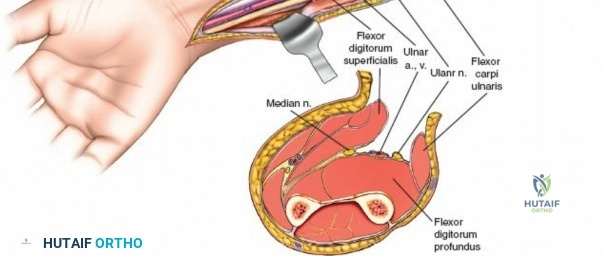

A thorough understanding of forearm anatomy is paramount for safe and effective fasciotomy. The forearm is typically divided into four primary osseo-fascial compartments, although some classifications may describe five:

- Superficial Volar (Flexor) Compartment: Contains pronator teres, flexor carpi radialis (FCR), palmaris longus, flexor carpi ulnaris (FCU), and flexor digitorum superficialis (FDS). The median nerve and ulnar artery course deep to this compartment, but their branches may be superficial. The fascia overlying this compartment is robust.

- Deep Volar (Flexor) Compartment: Deep to the FDS, this compartment houses flexor digitorum profundus (FDP), flexor pollicis longus (FPL), and pronator quadratus (PQ). The anterior interosseous nerve (AIN), a branch of the median nerve, and the anterior interosseous artery (AIA), a branch of the ulnar artery, are key structures here. The median nerve, deep to the FDS, is a critical structure that requires protection. The ulnar nerve and artery run along the ulnar border.

- Dorsal (Extensor) Compartment: Contains the extensor carpi ulnaris (ECU), extensor digiti minimi (EDM), extensor digitorum communis (EDC), and supinator. The posterior interosseous nerve (PIN), a branch of the radial nerve, courses through the supinator and then becomes the primary innervation for the dorsal compartment musculature.

- Lateral (Mobile Wad) Compartment: Also known as the mobile wad of Henry, this compartment contains the brachioradialis (BR), extensor carpi radialis longus (ECRL), and extensor carpi radialis brevis (ECRB). The superficial radial nerve runs deep to the brachioradialis in its distal third.

This image depicts the initial incision through the skin and subcutaneous tissue, exposing the underlying superficial fascia. -

Release of Superficial Volar Compartment: The superficial investing fascia of the forearm is carefully incised longitudinally throughout the length of the exposure. This releases the pronator teres, FCR, palmaris longus, FCU, and FDS.

- Proximally: Identify and protect the median nerve as it passes between the two heads of the pronator teres. The superficial head of the pronator teres can be released to facilitate access to the deep compartment. The Lacertus Fibrosus (bicipital aponeurosis) should also be released as it can be a source of compression.

- Mid-forearm: The FDS muscle bellies are prominent. Ensure the fasciotomy extends across the full width of the compartment.

Here, the superficial volar fascia has been incised, demonstrating decompression of the superficial flexor muscles. Note the muscle bulging as pressure is released.

Exposure and Release of Deep Volar Compartment: This is the most critical and potentially challenging step. The median nerve and ulnar artery lie deep to the superficial flexor muscles.

- Median Nerve Protection: Retract the FDS radially. The median nerve typically lies beneath the FDS. It must be carefully identified and protected.

- Ulnar Nerve and Artery Protection: The ulnar nerve and artery run along the ulnar border, deep to the FCU. They are usually not directly in the field of the primary fasciotomy, but their fascial envelopes should also be released.

- Accessing the Deep Compartment: Separate the FDS radially from the FCU. Retract the FDS radially and the FCU ulnarly. The deep volar compartment, containing FDP, FPL, and PQ, is now accessible. The fascia overlying the FDP and FPL must be meticulously incised longitudinally. This deep release is crucial for adequate decompression.

This image illustrates the deeper dissection. The superficial flexor muscles (FDS) are retracted, exposing the median nerve and the underlying deep volar compartment. Note the care taken to protect the median nerve.

The median nerve and ulnar artery/nerve must be completely unroofed to ensure adequate decompression. This often requires releasing the entire carpal tunnel proximally to ensure distal decompression of the median nerve.

This detailed view highlights the median nerve (retracted by the yellow vessel loop) and the extensive release required, extending distally to encompass the carpal tunnel, ensuring complete decompression.Ensure that the deep fascia separating the FDS from the FDP and FPL is completely released. The anterior interosseous nerve and artery lie on the interosseous membrane and should also be decompressed by releasing the fascia overlying the deep flexors.